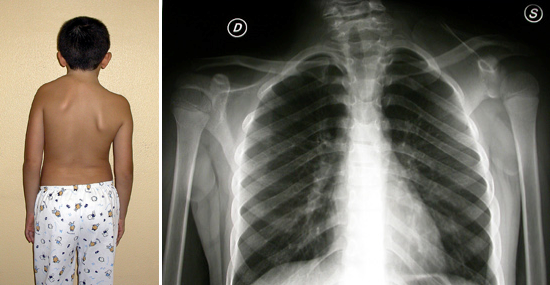

- muscolari (assenza congenita del muscolo serrato anteriore, ipotrofia del deltoide in esiti di paralisi ostetrica, fig. 3)